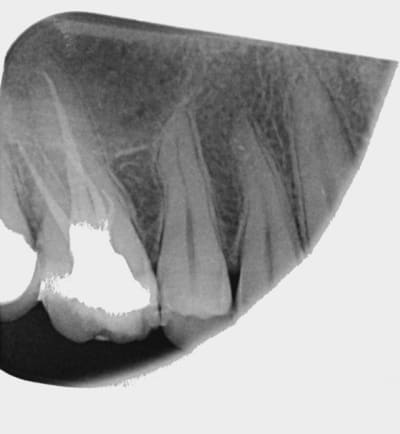

ici ça a cassé... je l'avais pourtant bien cathétérisé mais une seule erreur d'appui un peu forte et hop le protaper ne pardonne pas... c'est très blasant car du coup j'ai l'impression d'avoir fait une grosse merde... à suivre mais avec le bol que j'ai je compte bien sur une pêche en mésiale dans 6 mois...

Bien sûr, quand on voit la radio ppost-op c'est facile mais tu n'as pas ouvert assez l'entrée canalaire !!

On voit bien la grosse courbure de l'entrée de ta racine, ça ne pardonne pas, n'importe quel instrument de rotation continue aurait cassé.

Il aurait fallu ouvrir et supprimer le triangle de dentine avec des US ou des gates.

C'est récupérable avec un microscope et des US si jamais un jour ça se passe mal !

Comme cela a été dit plus haut, il faut beaucoup plus évaser l'entrée canalaire, en cherchant surtout à redresser la partie coronaire des canaux afin de permettre une pénétration plus "droite" des instruments... Cela enlève une première courbure et donc des contraintes inutiles.